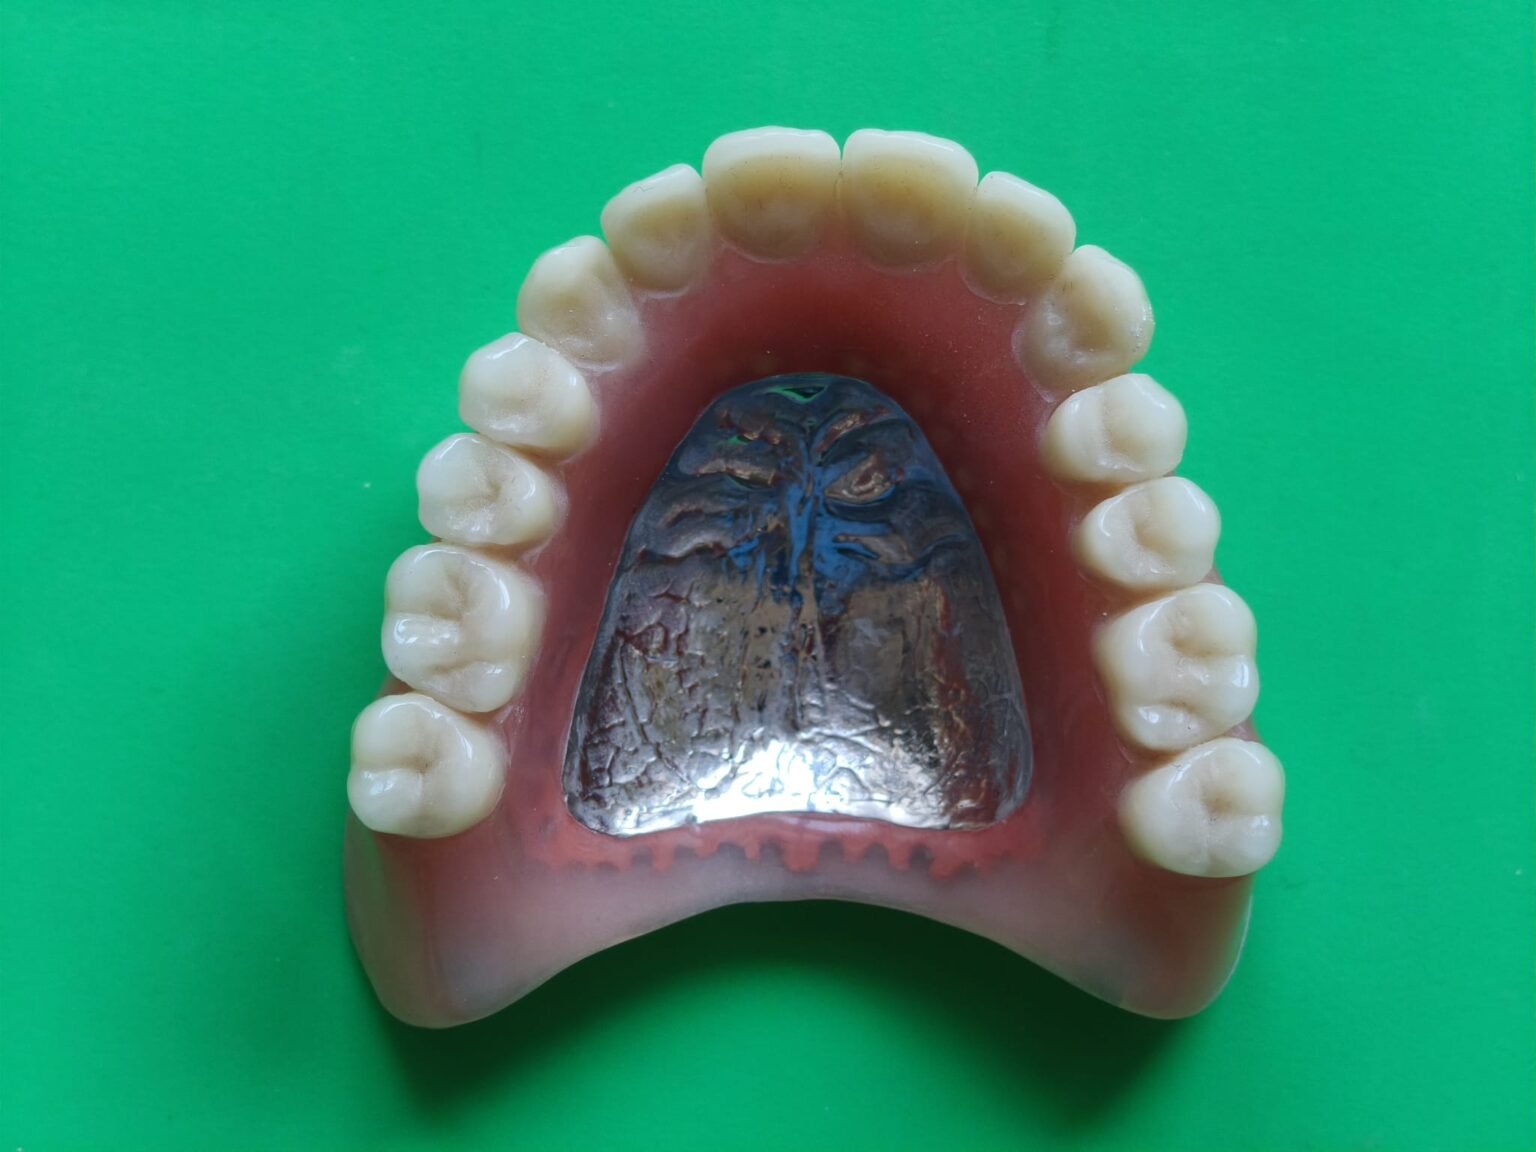

Eine Totalprothese muss nicht nur ersetzen, sondern auch die Funktion des stomatognathen Systems verlässlich stabilisieren. Grundlage dafür ist eine Prothesenbasis, die die individuellen anatomischen Gegebenheiten präzise aufnimmt und eine gleichmäßige Lagerung ermöglicht. Die Gestaltung der Randbereiche wird so ausgearbeitet, dass Bewegungen der Muskulatur berücksichtigt werden und die Prothese in dynamischen Situationen sicher geführt bleibt.

Ein wesentlicher Schwerpunkt liegt auf der Zahnaufstellung: Die statische und dynamische Okklusion wird so angelegt, dass Kaukräfte kontrolliert abgeleitet werden und das Prothesenlager nicht unnötig belastet wird. Besonders im ästhetisch sichtbaren Bereich achten wir auf Formen, Achsenstellungen und eine natürliche Lichtführung, um ein authentisches Erscheinungsbild zu erreichen, das sich harmonisch ins Gesicht integriert.

Auch funktionelle Parameter wie Zungenraum, Phonetik und Lippenunterstützung fließen in die Gestaltung ein. Das Ziel ist eine Versorgung, die im Alltag zuverlässig funktioniert, gut toleriert wird und den Patienten sowohl funktionell als auch ästhetisch dauerhaft begleitet.